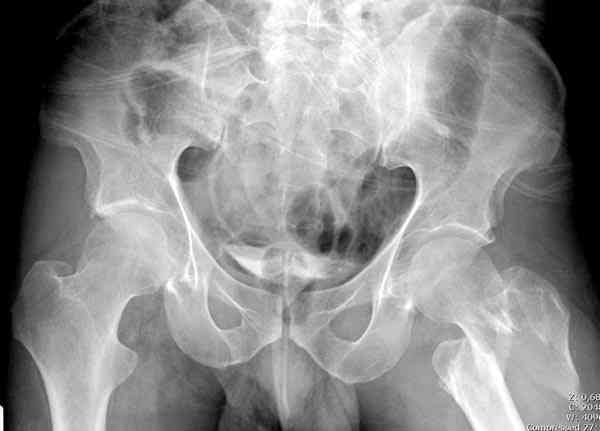

Применили проксимальную Synthes Locking plate, из-за множественных фрагментов посчитали более приемлемым в этом случае (клиника университетская, резиденты должны имет возможность созерцать разные варианты остеосинтеза).

Перелом из четырех фрагментов, не стабильный (лекция Michael R. Baumgaertner, http://www.hwbf.org/ota/bfc/baumg/exp.htm), нужна стабильная фиксация.

Фиксация таких нестабильных чрезвертельных и reverse obliquity субтрохантерик переломов всегда была сложной задачей и ранее использовали Blade Plate. Но многие локальные общие ортопеды, к которым, в основном поступают такие больные, имели трудности с применением импланта, где необходимо было точная калькуляция по введению Blade и поэтому Synthes разработал Proximal Locking plate как альтернативу, где три проксимальные шурупа в разных направлениях создают концепцию угловой стабильности Blade Plate.